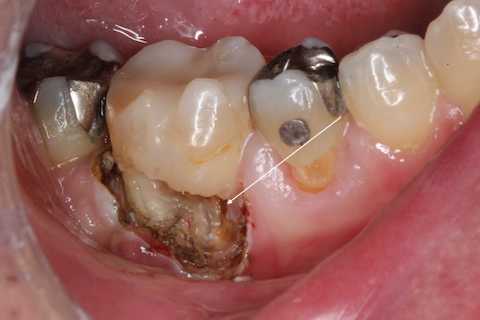

残根上のCR8 2025.10.28